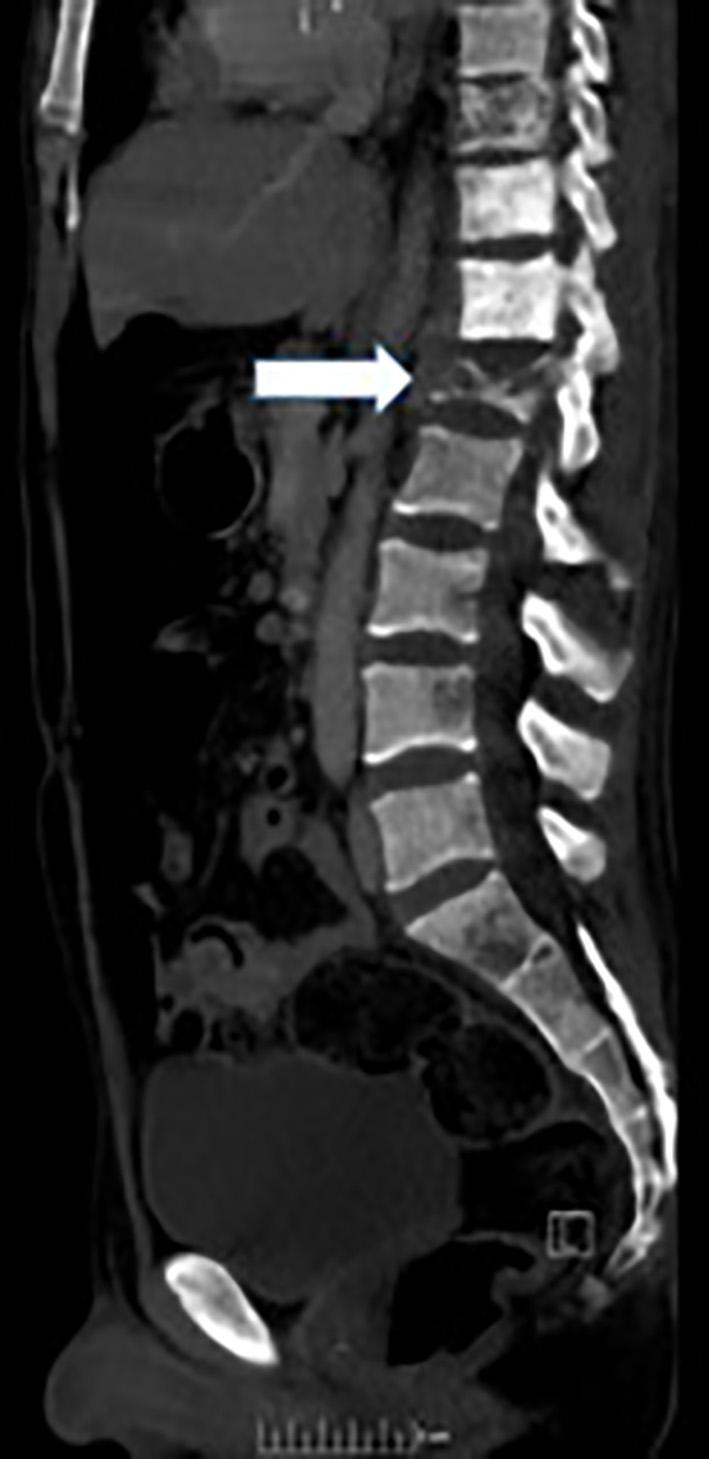

Magnetic resonance imaging (MRI) of the spine reported an epidural mass at T12-L1 level with spinal canal stenosis at T12 level (Fig. 1). Further workup included CT of chest/abdomen and pelvis which showed a large anterior mediastinal mass measuring 8.4 × 5.9 cm (Fig. 2), mixed lytic/sclerotic bony lesions in the spinal bodies from T10 to L1 (Fig. 3), the iliac crests, left sacrum, and the left ischial tuberosity and left supraclavicular lymphadenopathy (Fig. 4). The differential at that time inclined towards germ cell tumor and lymphoma and decision was made to biopsy the left supraclavicular fossa lymph node.

Figure 4. CT image depicting left supraclavicular lymphadenopathy/mass.